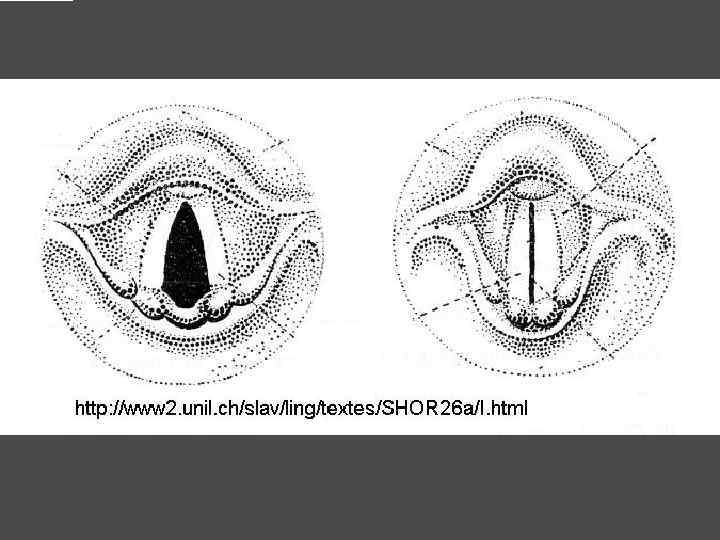

ОСЛОЖНЕНИЯ ХИРУРГИЧЕСКОГО ЛЕЧЕНИЯ ►Поражение возвратного нерва, приводящее к параличу голосовой связки на стороне поражения, как следствие – изменение тембра голоса, сужение голосовой щели, затруднение дыхания. ► Кровотечение. ►Тиреотоксический криз. ► Гипопаратиреоз. ► Рецидив тиреотоксикоза. ► Формирование порочного рубца.